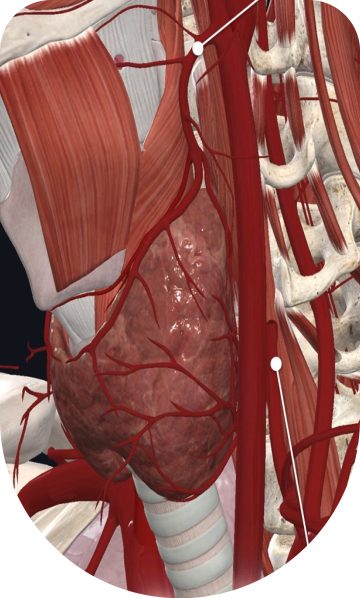

Endoscopic Thyroid Surgery (ETS) is a new surgical method for thyroidectomy, minimizing invasive techniques, while offering the safest and most aesthetic outcome for treatment of thyroid diseases.

There are many types of thyroid disorders ranging from benign nodules to malignancies, which require surgical treatment when medical treatment falls short. Endoscopic Thyroid Surgery has several advantages over standard surgical thyroidectomy. As this technique is minimally invasive, patients experience lesser pain, faster recovery and an aesthetically pleasing result, making it ideal for people who want to minimise visible scarring.

Endoscopic Thyroid Surgery begins with a detailed pre-operative assessment, including imaging and fine-needle aspiration cytology if required. The surgery is typically performed under general anaesthesia. Small incisions are made in inconspicuous areas like the axilla, chest, or behind the ear, through which a high-definition endoscope and specialized instruments are introduced. The surgeon carefully excises the targeted thyroid tissue while monitoring critical structures such as the recurrent laryngeal nerve and parathyroid glands. The removed tissue is sent for histopathological analysis. The procedure concludes with meticulous closure of the incisions, ensuring optimal healing and minimal scarring.